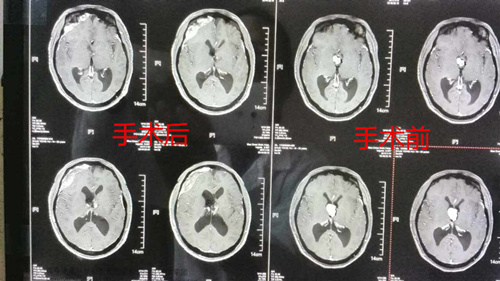

術(shù)后術(shù)前CT影像資料對比:腫瘤切除得十分干凈

術(shù)后兩次復(fù)查頭顱CT示:腫瘤切除干凈。第三、四天,患者精神癥狀消失,意識清醒,回答問題清楚,見人也會(huì)主動(dòng)打招呼,更沒有出現(xiàn)術(shù)前擔(dān)心的意識障礙、偏癱、多飲多尿等癥狀。和術(shù)前打針、剃頭、導(dǎo)尿等不配合,躁動(dòng)起來幾個(gè)人都按不住,更在術(shù)前剃頭時(shí)揚(yáng)言:“誰要剃我的頭,我就要先把誰的頭給剃了”已判若兩人。